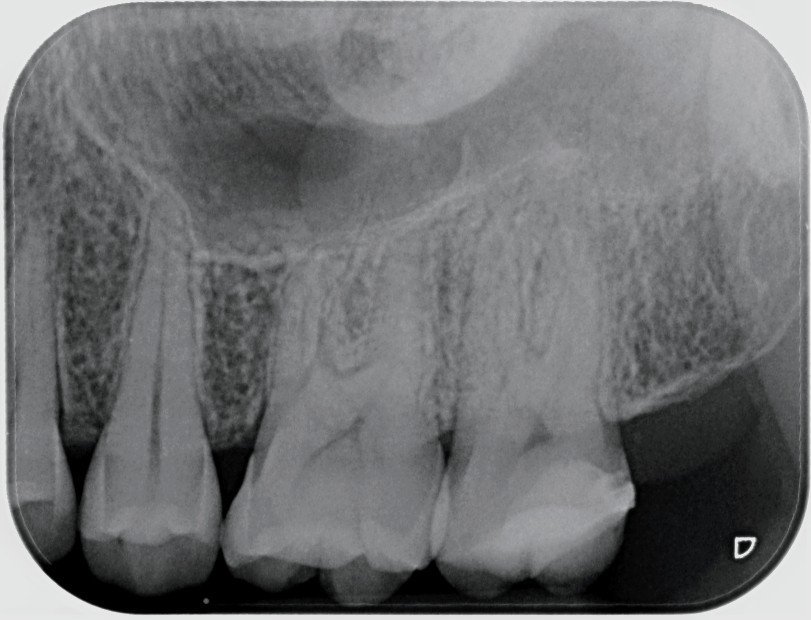

Здравейте, извадих два зъба 4 и 6 -ти при една зъболекарка в моя малък град, оказа се че не беше изчистила добре 6-ти зъб ,корена беше вътре на половина , ходих след това при хирург и ми извади това ,което е останало... но гледайки снимката ,която бях занесла се усъмни ,че и в четвърти имало нещо ,но не бил сигурен и трябвало да ми направи ревизия чак другия месец към края .... Аз днес си направих нова снимка ,защото вече нямам вяра на никой , 6 ти зъб изглежда изчистен, за четвърти виждам едно тунелче (така казано),което може би прилича на корен ,но пък на панорамната снимка на цялата дясна страна (защото той ме беше накарал да направя и такса ) , това тунелче  не се вижда и го няма ... Прикачвам последната снимка и моля зъболекар да ми каже има ли нужда от ревизия ,вижда ли се нещо? Мога да кача и панорамната на цялата стана ,пак казвам там не се вижда нищо на 4 ти зъб... Изобщо моля за второ мнение ,защото самия хирург не беше сигурен,може да има ,а може и да няма ,трябва да го отвори отново и да види ... То до края на другия месец ще се затвори ... Моля помагайте!

Някой може ли да ми каже нещо за последен 6- ти зъб. Имам предположение, но не съм специалист.

Много Ви благодаря! Вие зъболекар ли сте? Защо се вижда това тунелче ?

Защото е имало зъб там, костта ще се възстанови.